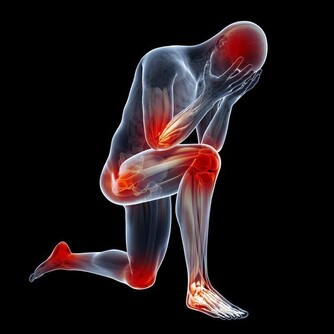

腎虛會導致人體的免疫能力降低,加速衰老,

腎臟一旦出現問題,那麼身體的各種疾病便會隨之而來。

早衰,健忘失眠,食欲不振,骨骼與關節疼痛,腰膝酸軟,不耐疲勞,乏力,視力減退,聽力衰減。